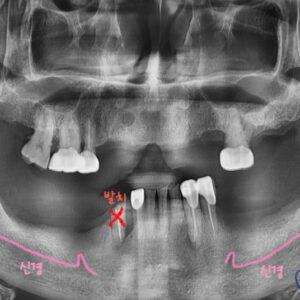

처음 내원 당시 다수의 치아 상실과 치조골 손상이 있으셨고

그로 인해 잔존치 또한 발치가 불가피한 상태이셨기에

추 후 다수의 임플란트가 필요하다고 판단되었고

임플란트의 정확한 위치와 안정성을 위해 네비게이션 임플란트를 진행하기로 하였습니다

발치가 필요했던 치아들은 발치를 진행한 후,

위 그림과 같이 3D-CT 사진을 통해

임플란트의 식립위치, 방향, 각도 등을 분석하여

네비게이션 임플란트 가이드를 제작합니다